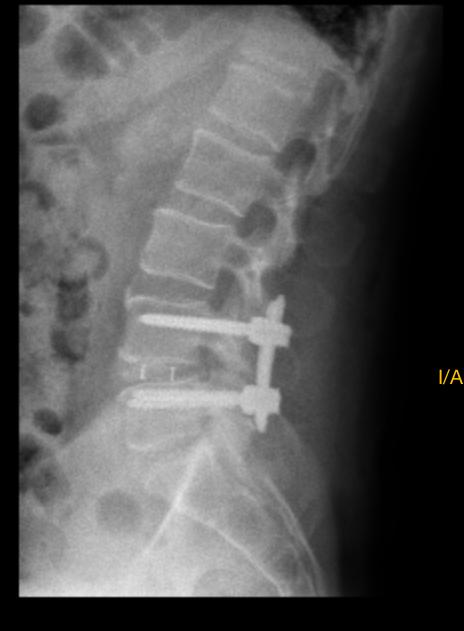

Radiografía lateral de columna lumbar con implantes tras cirugía MISTLIF

La Cirugía MISTLIF es una técnica de fusión lumbar mínimamente invasiva que permite acceder a la columna por un abordaje lateral unilateral (transforaminal), a través de pequeñas incisiones. Se realiza la extracción del disco intervertebral dañado y se inserta un implante (cage) con injerto óseo entre los cuerpos vertebrales, acompañado de tornillos y barras para estabilizar el segmento afectado.